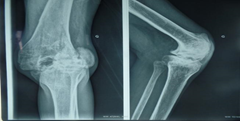

X- ray examination

In the majority of cases, the imaging examination found soft tissue swelling with irregular bone contours (Figure 5 & 6), destruction of bone cartilage or even a fracture in 6.66% of cases. No cases of epiphyseal deformation, subluxation or ankylosis were found.

Figure 5 Irregularity of joint surfaces.

Figure 6 Joint incongruence.

According to Klukowska and colleagues,26 the radiographic appearance of hemophilic arthropathies is strongly correlated with the number of hemarthrosis episodes. Strauss and colleagues14 had 21 cases of hemophiliacs with an average Peterson score of 7.3 with irreversible but non-disabling injury that is stage II. Molho and colleagues15 also reported a Peterson score of 13.5 with massive joint destruction in 116 severe hemophilia patients. We still have limitations on coagulation factors because prophylaxis depends on the availability or not of the supply from the foreign body. Sometimes, for example, we encounter administrative problems concerning the customs clearance of products. But also, we are frequently faced with a break in medication. Thus, we suggest close collaboration with local or foreign organizations so that we can ensure the continuity of treatment (Figure 7).

Figure 7 Erosion and joint destruction pronounced bone structure, fracture.